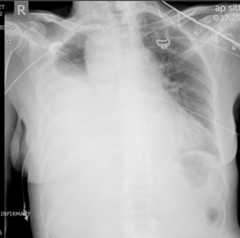

Massive right hemothorax

Chest X-ray showing a collection of fluid in the right pleural space, as illustrated by the opacified lung